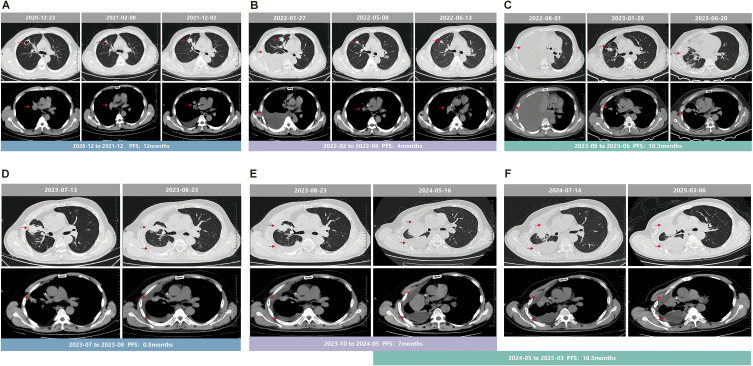

Results: This case report describes a patient with advanced non-small cell lung cancer (NSCLC). The patient was diagnosed with adenocarcinoma of the right upper lobe (T3N1M1a, stage IV). Next-generation sequencing (NGS) detected an EGFR exon 20ins, specifically P772_H773insGNP. The patient experienced disease progression despite multiple lines of therapy. Following multidisciplinary discussion, furmonertinib was initiated as sixth-line therapy. The best overall response was assessed as partial response (PR), and as of the last follow-up, the patient had achieved a progression-free survival (PFS) of 10.5 months.

Conclusion: This case represents the first report of a favorable response to furmonertinib in a patient with the EGFR exon 20ins subtype P772_H773insGNP, a near-loop mutation. EGFR exon 20ins mutations are highly heterogeneous, and different subtypes exhibit varying sensitivities to targeted drugs. Exploring individualized treatment approaches is of great clinical importance.